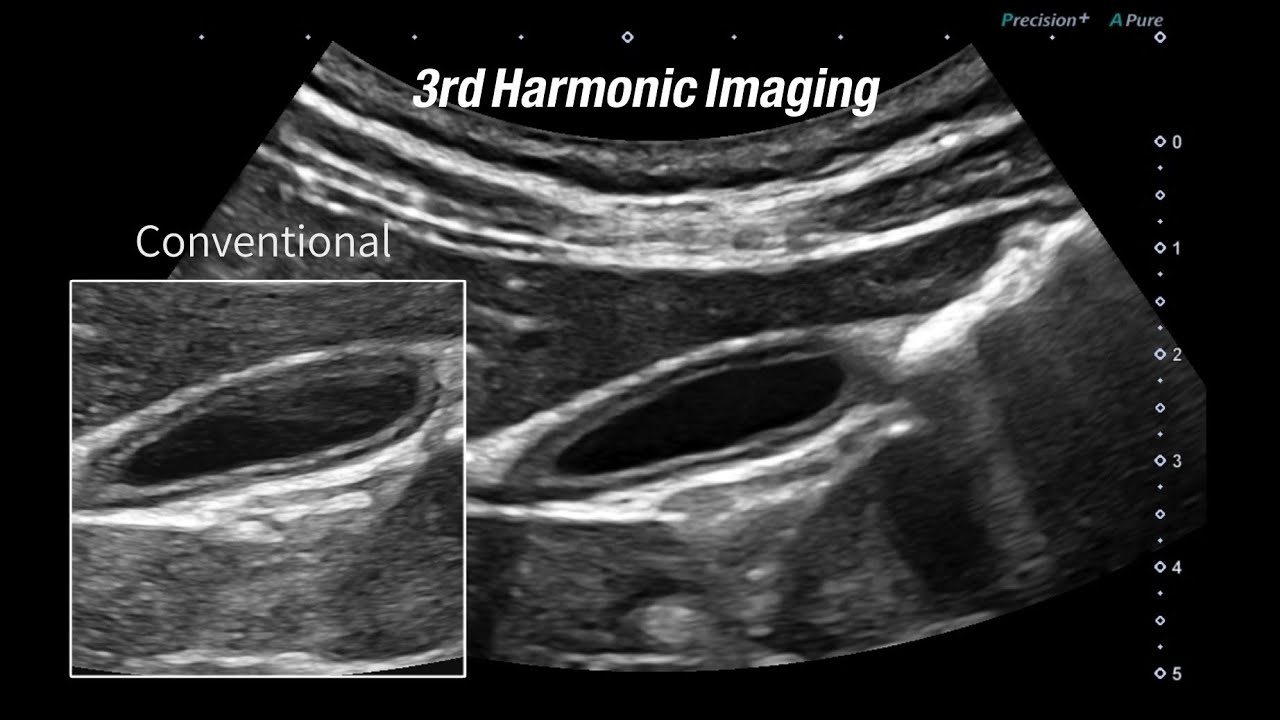

Imagen armónica

El ecógrafo escanea imágenes al doble o múltiplos de la frecuencia. Se usa para disminuir los artefactos (reverberación). También se encarga de mejorar la definición y se encuentra por defecto en la mayoría de los aparatos comercializados.